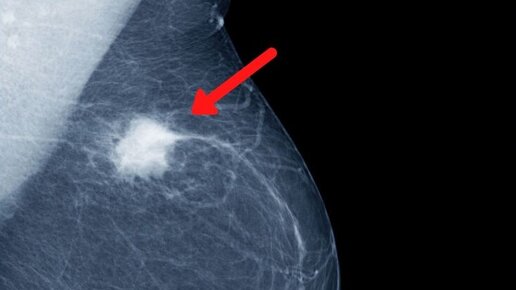

Золотым стандартом исследования груди на сегодняшний день является маммография (сокращенно ММГ) – это рентген молочной железы. Это наиболее доступный и дешевый вариант обследования, который хорошо ориентирован на поиск раковых и предраковых изменений в ткани молочной железы. Поэтому именно он используется для профилактических осмотров (диспансеризации). Что такое маммографический снимок? Смысл маммографии (ММГ) заключается в том, что рентгеновские лучи, когда проходят через разные ткани, рассеиваются по разному (чем более плотная ткань, тем сильнее рассеивание)...